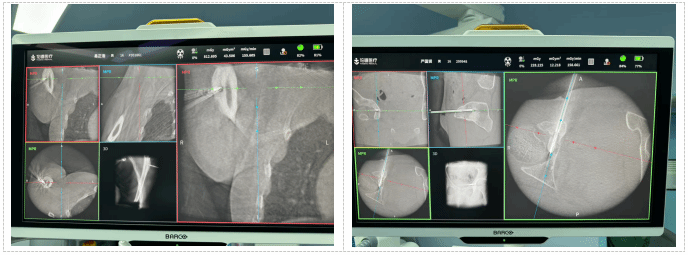

重大临床医疗成果(特等奖)——骨盆髋臼骨折精准微创诊疗体系的创建与推广应用

首席专家:创伤骨科负责人 樊仕才

项目简介:本项目构建了涵盖诊断、治疗与手术入路的全程微创诊疗体系。创新提出“骨盆骨折合并腰骶丛神经损伤”诊治理念,开发三维图像融合技术,并发明“个体化定制髋臼解剖接骨板”。团队研发4种符合国人解剖的骨盆髋臼解剖钢板,首创“腹直肌外侧入路”“直接后方入路”等微创术式,将手术切口从20厘米以上缩短至8–10厘米,显著提升手术精准度与康复效率。